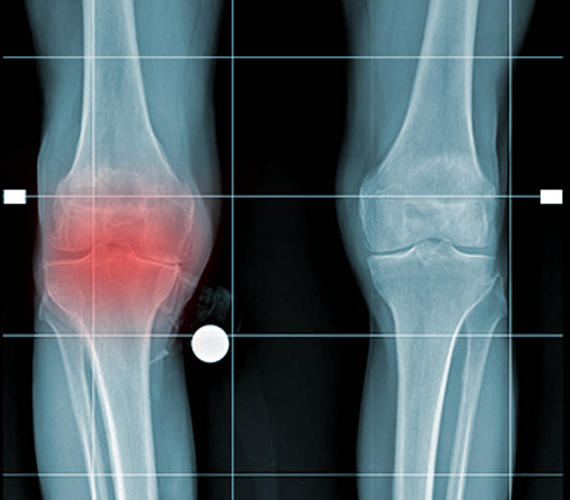

La protesi totale del ginocchio - prima dell'operazione

ARTROSI SEVERA

GINOCCHIO DESTRO